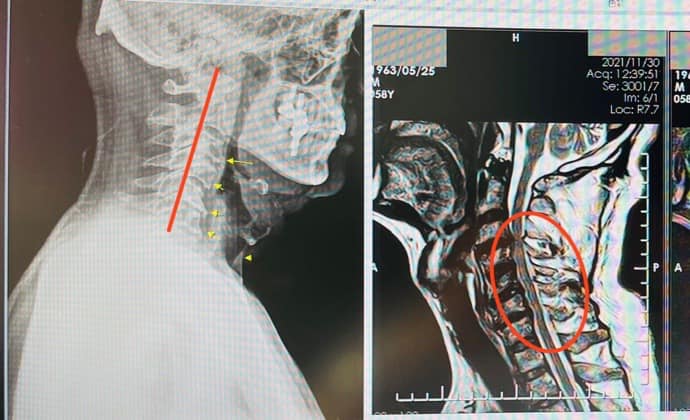

桃園市中壢的廖先生年紀約59歲,他在3個月前打高爾夫球受傷,受傷後很多天連續開始整天不定時的抽痛,晚上睡覺平躺都會痛醒,尤其是翻身和起身讓他感到極度的痛苦,找了很多方法、做過很多治療,但效果都不佳~,拍完核磁共振,大醫院骨科醫師都建議可能要開刀,但是復健多個月仍然沒有起色,變成只能整天都靠吃2~3顆的止痛藥生活,但自己其實都知道這只是安慰劑罷了,因為吃了還是一樣的不舒服!!

1.右側C3C4;C4C5;C5C6神經根型頸椎病

2.C3C4頸椎變型

3.慢性筋膜發炎疼痛